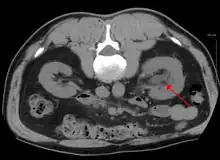

CT scan of bilateral hydronephrosis due to a bladder cancer

Massive hydronephrosis as marked by the arrow.- Renal ultrasonography of hydronephrosis[14]

- Stone causing hydronephrosis[14]

- Urine jets[14]